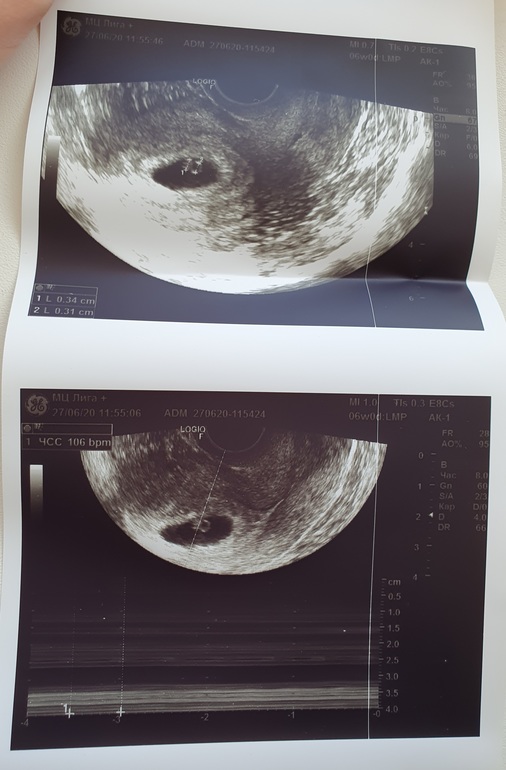

Подскажите, пожалуйста, у меня есть снимок с узи, как я понимаю где идёт измерение ЧСС( а может и нет, ничего в УЗИ не понимаю)

Так вот, в заключении УЗИ стоит ЧСС 110, переживаю что это очень мало, срок был 6.4 по УЗИ. Но у врача в заключении было несколько опечаток, по ктр в том числе. Я все надеюсь, что может и с ЧСС ошиблась.

Посмотрите, пожалуйста, может быть вы что-нибудь увидите. Потому что 110 я нигде не вижу на фото

Мой снимок с чсс в 6,2 недели выглядил так...